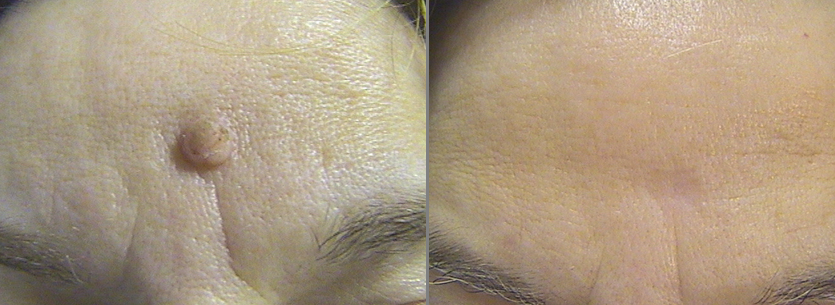

Фото: рубец на коже после удаления новообразования

Кроме того, если у вас чувствительная кожа, то после процедуры на ней могут появиться пузырьки и покраснения. Из-за этого метод не очень подойдет для деструкции новообразований с века, так как в этом месте очень нежная кожа.